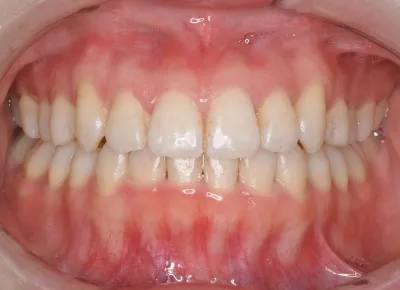

Before

After

治療期間

費用総額